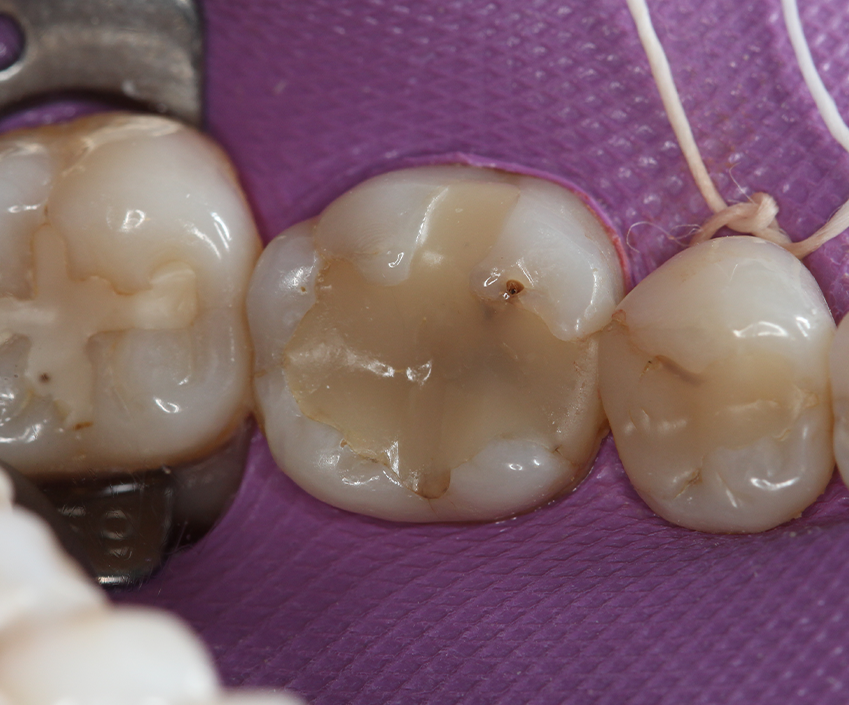

After initial X-ray (Fig. 2) and rubber dam isolation (Fig. 3), the previous restoration was carefully removed with a 1015 diamond bur (KG Sorensen) in order not to compromise the adjacent tooth. A metal matrix was used for protection. The cavity was cleaned with pumice (Fig. 4).

Fig. 3 Fig. 4